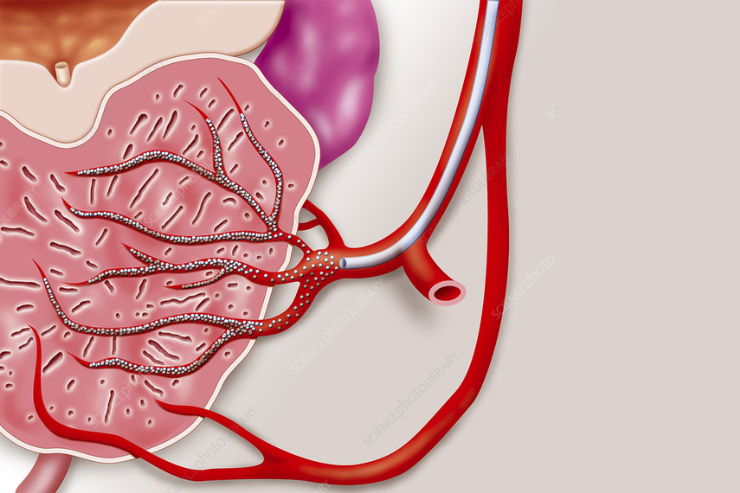

Prostate Artery Embolization

Prostate Artery Embolization is a minimally invasive procedure used to treat benign prostatic hyperplasia (BPH). It involves injecting small particles into the arteries supplying the prostate to block blood flow, causing the prostate to shrink. This reduces symptoms such as frequent urination and urinary obstruction, improving quality of life for patients with BPH.